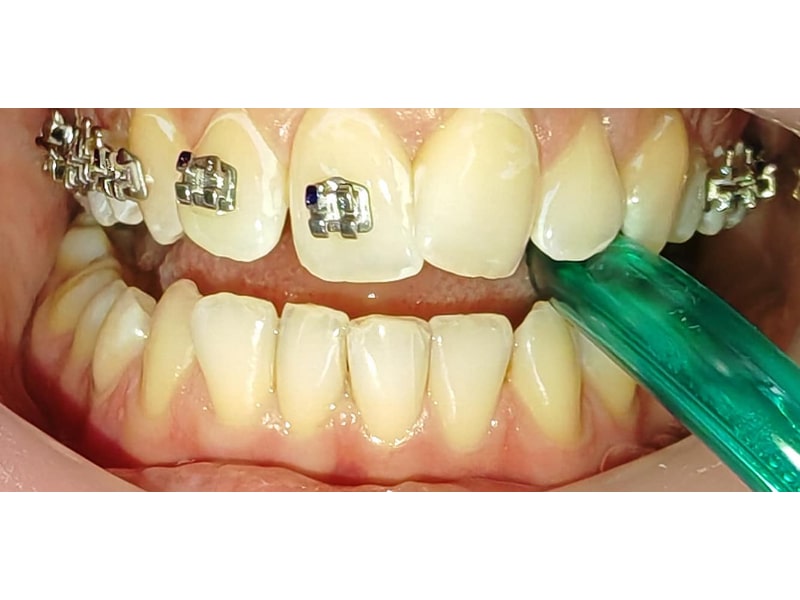

Ortodonție